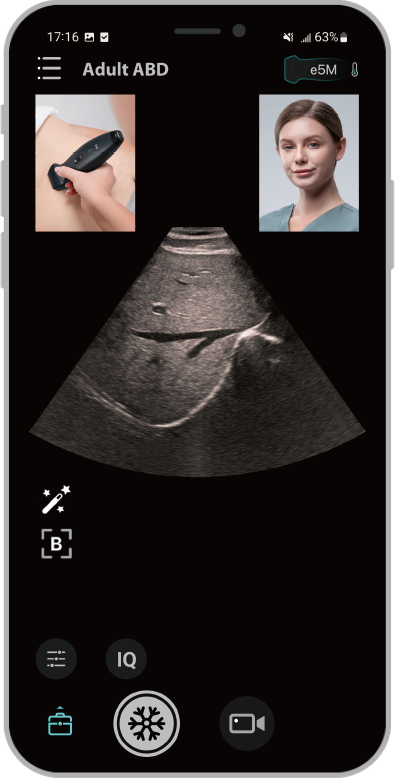

Door meerdere toepassingen te integreren, is de TE Air e5M geschikt voor scans van het gehele lichaam en kan deze in verschillende klinische scenario's worden ingezet. Dankzij het draadloze ontwerp kunnen altijd en overal hoogwaardige echografie?n worden gemaakt. De TE Air e5M is niet alleen veelzijdig. Het apparaat biedt ook een reeks slimme functies en trainingstools om vertrouwen en effici?ntie te vergroten.

1Gebruiksvriendelijk met een intu?tieve gebruikersinterface

2Verbetert effici?ntie dankzij bediening met ├®├®n hand

3Biedt oplossingen voor beheer van pati?ntgegevens

4Voltooit uw workflow door naadloze interconnectiviteit met uw informatiesysteem